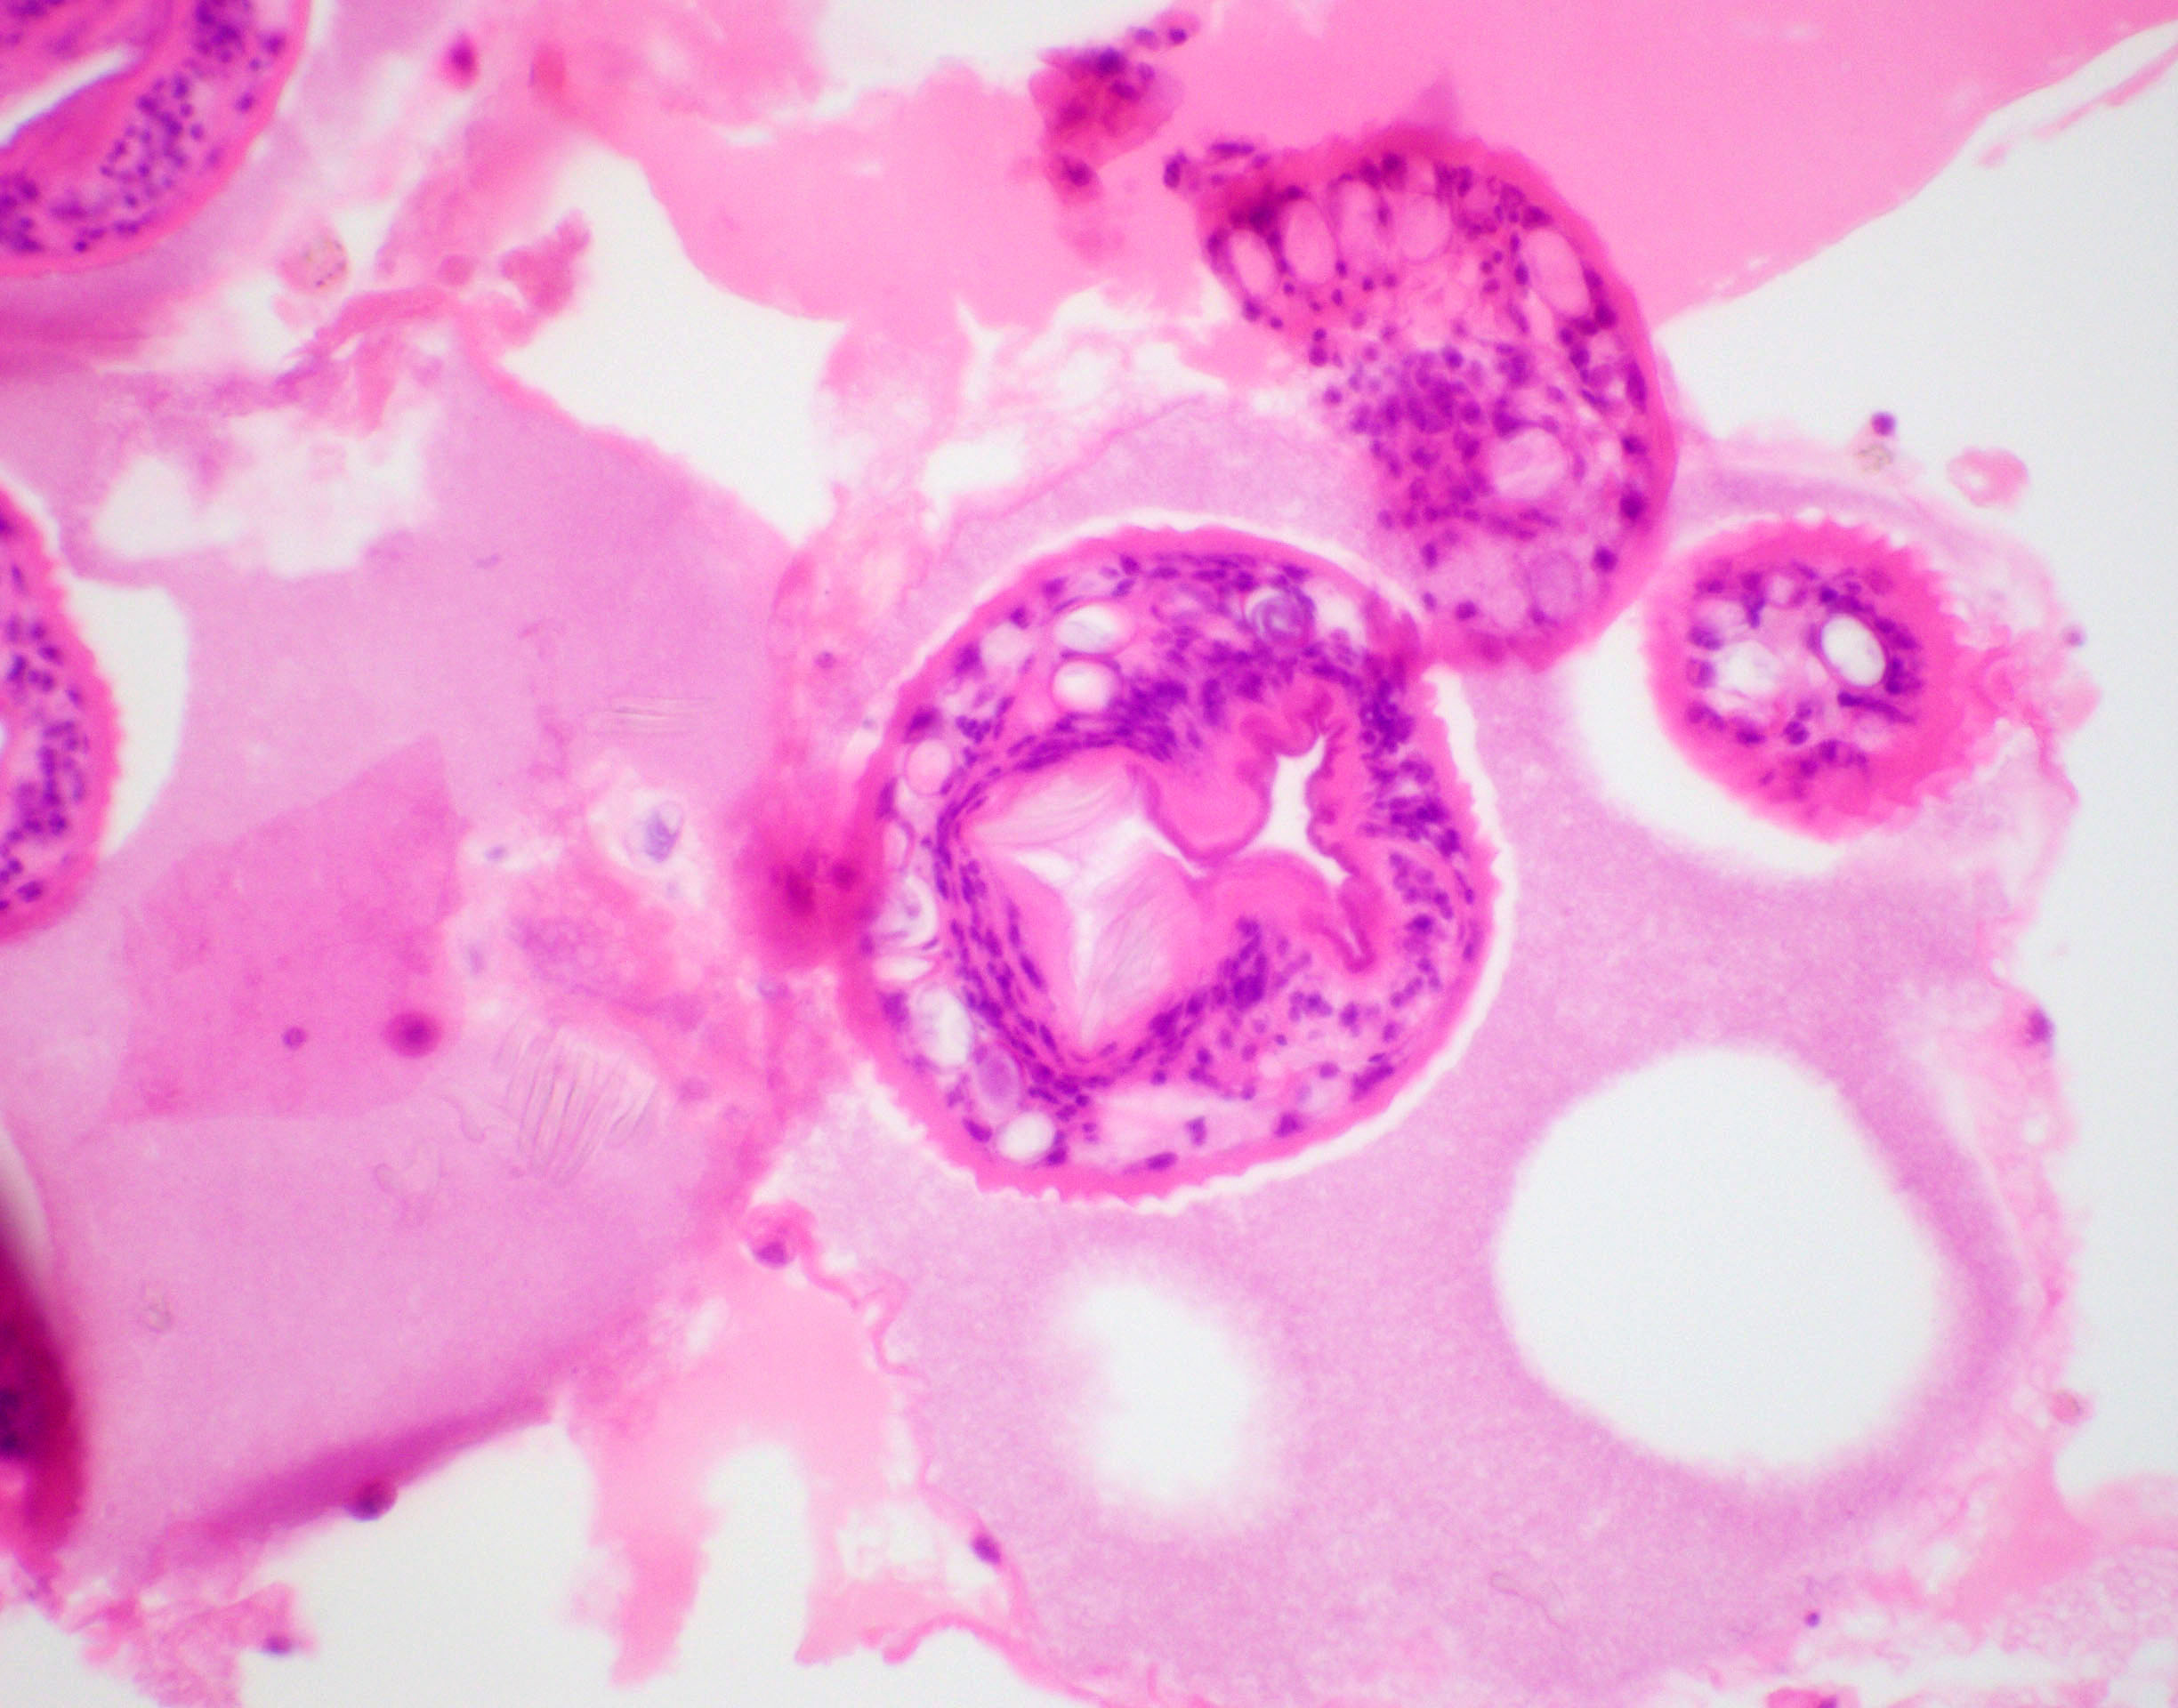

Microscopic (histologic) description

- E. granulosus

- Cyst wall has 3 structural components:

- Outer acellular laminated membrane (1 mm thick)

- Germinal membrane (a transparent nucleated lining)

- Protoscolices, attached to the membrane and budding from it

- Protoscolices are ovoid and contain hooklets (birefringent under polarized light) and a sucker

- Outer fibrotic layer with granulation tissue with increased eosinophils also exists

Microscopic (histologic) images